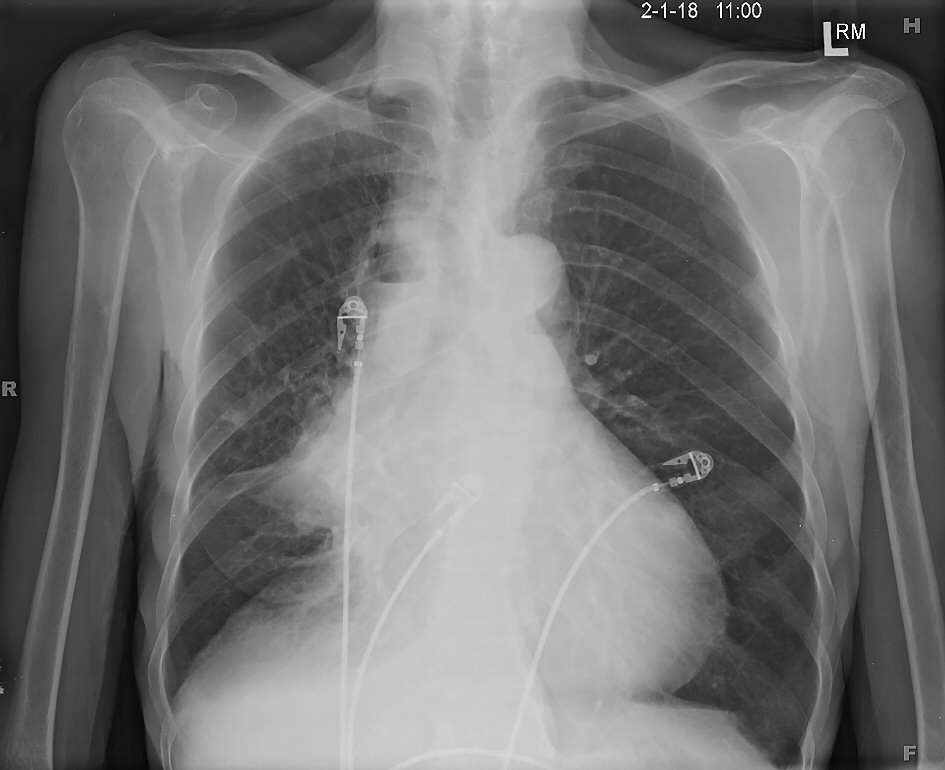

Figure 6. Posterior-anterior chest X-ray showing cavitary lesion with an air-fluid level in the right upper lobe and an enlarged cardiac silhouette.